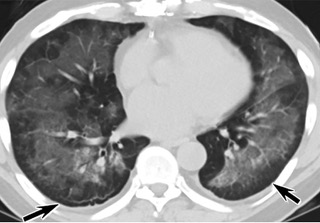

疑點一,電子煙患者的CT影像和臨床表現并不具有特異性。所謂美國電子肺炎患者,其實是對沒有其他合理診斷證據、吸食電子煙肺炎患者的統稱。這些患者在病發前90天內吸食了電子煙,尤其值得注意的是,部分患者的CT影像特征和臨床表現與病毒性肺炎患者極其相似。

中、下肺軸位CT平掃顯示毛玻璃樣混濁伴胸膜下保留(箭頭)。(同一病人CT影像)